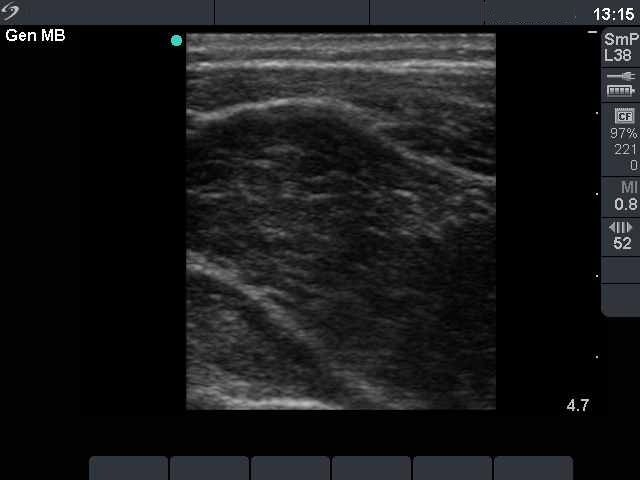

Ultrasonography. Both lobes were extremely enlarged, the largest diameter of the right lobe exceeded 12 cm. The whole thyroid was hypoechogenic and displayed fibrotic changes. No vascularization could be detected on Doppler mode.